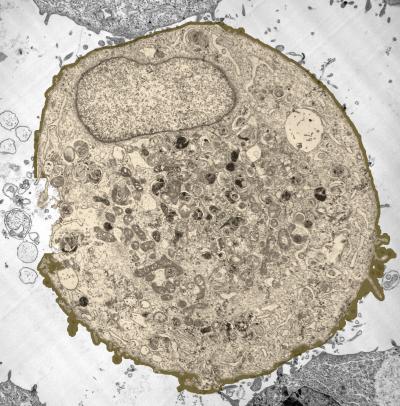

Using five different microscopy techniques, the researchers showed that the violent collapse of bubbles – an effect caused by the ultrasound – creates enough force to open holes in the membranes of cells suspended in a liquid medium. The holes, which are closed by the cells in a matter of minutes, allow entry of therapeutic molecules as large as 50 nanometers in diameter – larger than most proteins and similar in size to the DNA used for gene therapy.

"The holes are made by mechanical interaction with the collapsing bubbles," said Mark Prausnitz, a professor in the School of Chemical and Biomolecular Engineering at the Georgia Institute of Technology. "The bubbles oscillate in the ultrasound field and collapse, causing a shock wave to be released. Fluid movement associated with the resulting shock wave opens holes in the cell membranes, which allow molecules from the outside to enter. The cells then respond to the creation of the holes by mobilizing intracellular vesicles to patch the holes within minutes."

Prausnitz and collaborators Robyn Schlicher, Harish Radhakrisha, Timothy Tolentino, Vladimir Zarnitsyn of Georgia Tech and Robert Apkarian (now deceased) of Emory University set out to study the phenomenon in detail using a line of prostate cancer cells. They used scanning and transmission electron microscopy of fixed cells and two types of optical microscopy of living cells to assess ultrasound effects and cell responses.

Beyond demonstrating that ultrasound punched holes in cell membranes, the researchers also studied the mechanism by which cells repair the holes. After the ultrasound exposure, they introduced into the cell medium a chemical not normally taken up by the cells. By varying when the chemical was introduced, they were able to determine that most of the cells had repaired their membranes within minutes.